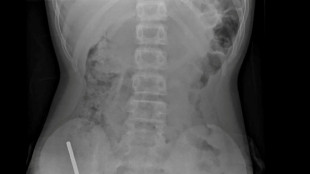

The 30-year-old lives with several chronic and degenerative diseases, including kidney failure, and spends 10 hours a day hooked up to a dialysis machine to survive.

After undergoing two failed kidney transplants, and with no possibility of being cured, in August she launched her campaign for Mexico to give people the right to die with dignity.

"I would take 15 days to die, but those would be 15 days of agony and suffering because your whole body is poisoned. You can drown in your own liquids. It is a very undignified death," said Martinez.

To stop dialysis, she said, would be a form of passive euthanasia -- withholding treatment that would keep a dying person alive.